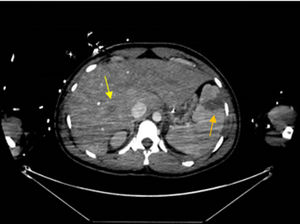

De forma paulatina la paciente va estabilizándose tanto desde el punto de vista respiratorio como del hemodinámico, permitiendo trasladarla para realizar estudio de extensión con tomografía axial computarizada (TAC), en el que se aprecian múltiples abscesos pulmonares (fig. 1), dos abscesos hepáticos e infarto esplénico (fig. 2)1; cráneo sin hallazgos.